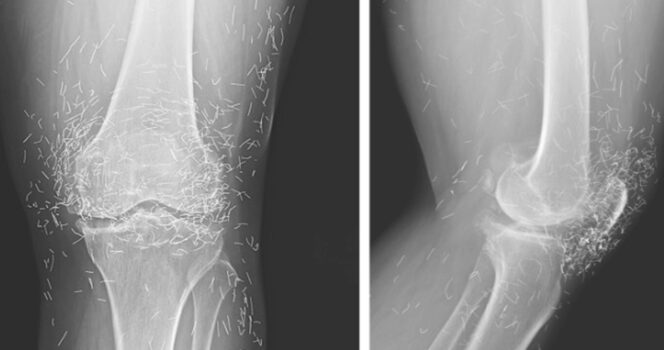

When a 65-year-old South Korean woman went in for knee pain, doctors weren’t expecting to strike gold. But that’s exactly what they found.

So she turned to acupuncture, according to a case published in the New England Journal of Medicine.

Acupuncture, a centuries-old alternative treatment, involves inserting needles into the body at specific points to relieve pain or treat illnesses. In this case, the needles— presumably made of gold — were intentionally left in her knees for continued stimulation.

He also warned that embedded needles can complicate X-ray readings. “The needles may obscure some of the anatomy,” Guermazi said in 2013.